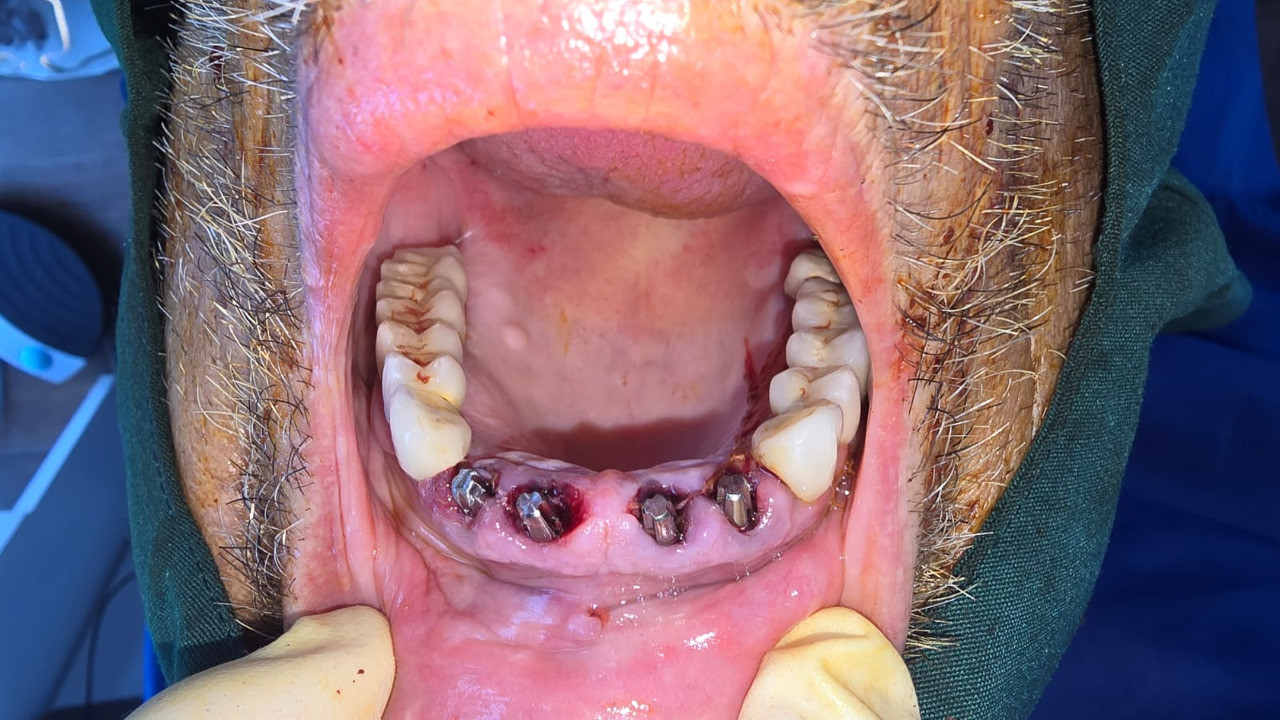

Implantología Estratégica Cortico Basal

Envíado por Dr. Rene Mauricio León Aparicio